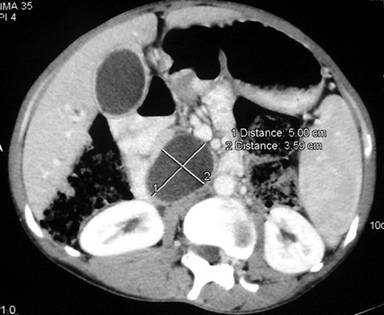

Plain X-ray of the abdomen revealed classical curvilinear calcification in only one patient with a hydatid cyst in the pancreatic body (Figure 1). Ultrasonographic examination which recorded the site, size and extent of the lesions, documented the cystic lesions as anechoic rounded structures in all cases. An abdominal CT scan documented the cysts as spherical hypodense space-occupying lesions. All the lesions were solitary, measuring 26-50 mm in diameter (mean 36.7 mm). Five lesions were cystic with thin walls and one lesion appeared as a multiseptated cyst. Magnetic resonance imaging for defining the lesion and its relationship with the pancreatic duct was performed in three patients (two lesions in the head and one in the body of the pancreas). Two lesions were located in the head (Figure 2, 3, 4, 5), two in the body (Figures 6 and 7) and two in the tail region of the pancreas (Figure 8). In two cases, a preoperative diagnosis was possible due to the presence of classical features which also included a concomitant hydatid cyst in the liver in one patient. All patients underwent surgical exploration; intraoperative cyst puncture for aspiration cytology was successful in three cases (two cases with cysts in the head and one case with a cyst in the body of the pancreas); the results of cytological examination were positive in all cases. A fragmented laminated membrane was observed in two patients, scoliosis in three and hooklets in one patient (Figure 9). The laminated membrane was seen as a foliated, acellular, pale, eosinophilic structure which stained strongly positive with periodic acid Schiff staining and negative with alcyan blue staining. The hooklets had a characteristic shape presenting as a blade, a guard and a root. They were not stained with Papanicolaou stains and their appearance was enhanced by turning down the microscope condenser. There were no complications after diagnostic aspiration. In all three cases, the aspirated fluid was colorless and contained a mean sodium level of 128 mEq/L (range: 128-130 mEq/L), chloride level of 69 mEq/L (range: 65-70 mEq/L) and potassium level of 5.8 mEq/L (range: 5.4-6.3 mEq/L). Cysts in the distal pancreas observed in the two patients were treated by a distal pancreatectomy with splenectomy. Cysts in the body were treated by a pericystectomy in one patient (Figure 10) and a central pancreatectomy in another patient. Cysts in the head region in two patients were treated with evacuation, partial cystectomy and tube drainage of the cavity after protecting the surgical area with a scolicidal solution (Figure 11). Both patients underwent T-tube drainage of the common bile duct; there was rapid regression of the jaundice in these patients. The T-tube cholangiogram confirmed the free flow of bile into the duodenum; the tubes were eventually removed in the third postoperative week. Postoperative confirmation of the hydatid cysts was obtained on the basis of the histopathological findings. There were no postoperative complications; all patients recovered uneventfully. The antihelminthic drug, albendazole, was administered postoperatively (10 mg/kg body weight/day) in all cases for a period of 6 months. All the patients were followed up at three-month intervals and each patient underwent clinical examination, abdominal ultrasonography and indirect hemagglutination tests; no patient had cyst recurrence or dissemination. The mean follow-up time was 58.7 months (range: 4-120 months).

Figure 6. Contrast-enhanced computed tomography scan demonstrating a solitary cystic lesion (33 mm) in the body of the pancreas with internal daughter cysts (Patient #3). |